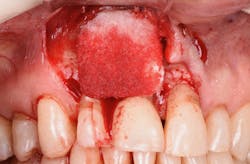

Figure 9: Initial presentation prior to crown lengthening

Figure 10: Immediate post-op hard- and soft-tissue crown lengthening with laser